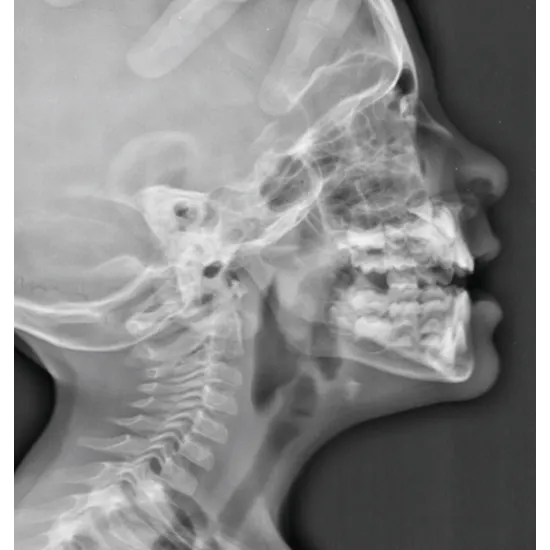

X-rays with lateral nasal views identify the nasal fractures. The nasal fractures are frequently seen in the adults and also in some children.

This X- ray test uses the plain images with a lateral nasal view to diagnose your nasal fractures. This X ray test with the lateral view is said to have an 82% reliability rate and produces accurate results repeatedly.

Standard imaging method that is used to diagnose any nasal fractures is the direct radiography.

The lateral view would also use x-rays that to evaluate the nasal dorsum and the occipital views that will be used for lateral nasal walls.

The nasal bones are said to be the most frequently fractured in bones of the maxillofacial area due to any relative weakness and outward projection of nose on the face.